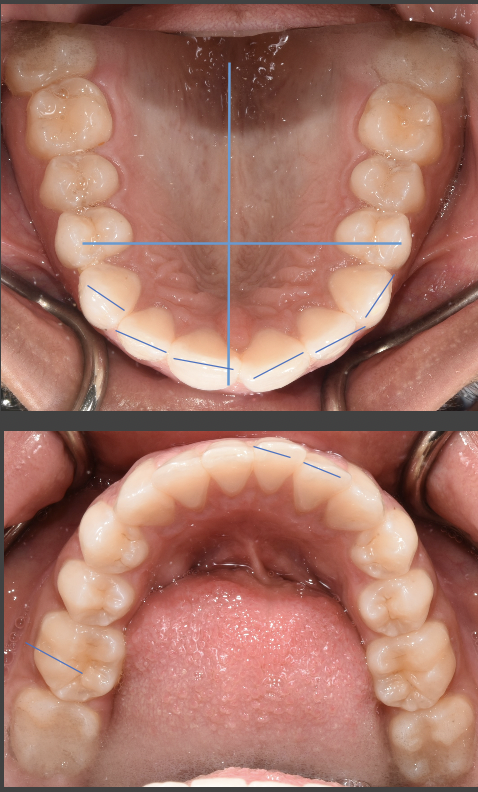

Hi I’ve been having issues with my jaws the feeling of them being extremely sore and I also cannot bite completely down on one of my sides of my mouth my teeth don’t look perfect or good they look “normal” I guess you can call it what would fix this ? Do I need braces ? My friends tell me I have a slight overbite but I can’t physically tell and I also bite the sides of my mouth and the inside of my lip a lot while eating.. what should I do ? I go to the dentist soon but is it best for me to go to a dentist or orthodontist?

From the picture submitted, it appears that you are biting edge to edge, which does need to be addressed and corrected by your orthodontist. It is ideal to mention these symptoms to your dentist at your check up appointment. Your jaw should not be sore on a regular basis. This could be a symptoms of a dysfunctional temporomandibular joint (TMJ). While the small spaces are more cosmetic, the uneven bite, soreness and inability to completely close on one side all raise red flags. Its best to correct these issues now, rather than to wait for them to worsen or for restorative treatment to be needed in addition to orthodontics due to wear patterns.